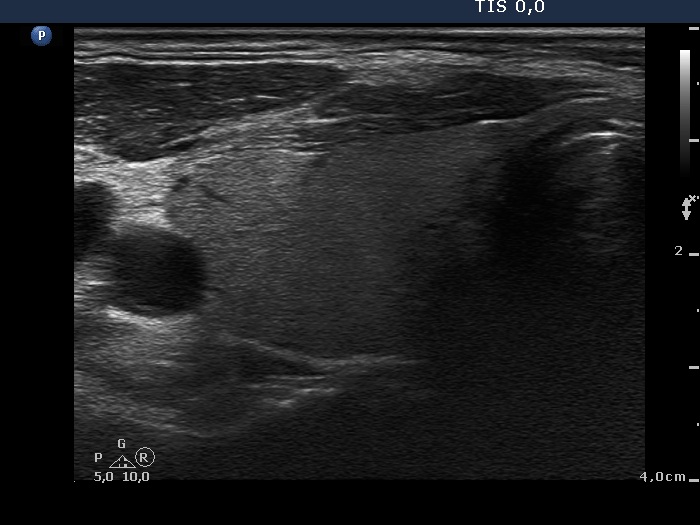

Lymph nodes in the neck - Case 154 (ultrasonographic picture 1)

Right lobe, horizontal view

Right lobe, transverse scan. The thyroid is intact.